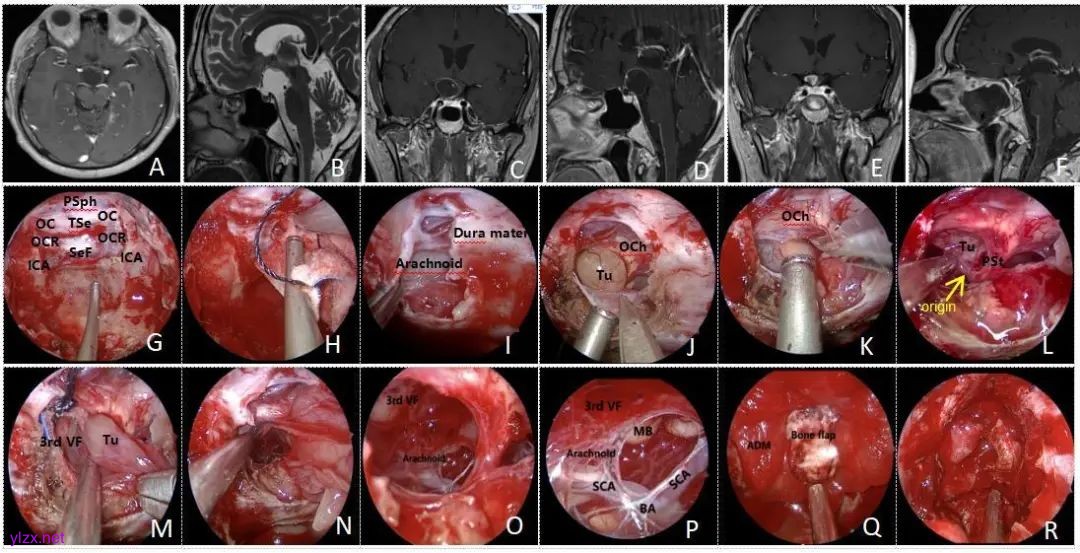

EEEA手术:内镜经鼻扩展入路适用于鞍膈下及垂体柄附近的较浅肿瘤,利用垂体柄-视交叉间隙进入手术区域。该手术在直视下分离肿瘤,并对鞍底进行修补,尤其适用于Q-CP和S-CP类型的病例(图3)。

图3 内镜经鼻扩展入路切除颅咽管瘤资料 PSph,蝶骨平台;OC,视神经隆起;TSe,鞍结节;OCR,视神经颈内动脉陷凹;SeF,鞍底;ICA,颈内动脉;Dura mater,硬脑膜;Arachnoid,蛛网膜;Tu,肿瘤;OCh,下丘脑;origin,起源;PSt,垂体柄;3rd VF,第三脑室;MB,乳头体;SCA,大脑后动脉;BA,基底动脉;ADM,人工硬脑膜;Bone flap,骨片。A~D,术前MRI提示鞍上囊性占位性病变,肿瘤起源于垂体柄,视交叉受压上抬,考虑为颅咽管瘤,QST分型为S型;E~F,术后6个月MRI未见肿瘤残留,可见垂体柄在位,未见复发;G,磨除蝶窦前壁及鞍结节骨质,暴露鞍底、鞍结节、蝶骨平台等结构;H,海绵间窦止血;I,剪开鞍底及鞍结节硬膜并分离硬膜与蛛网膜粘连;J~K,分离蛛网膜与肿瘤间隙;L,减容肿瘤后见肿瘤起源于垂体柄中下段;M~N,三脑室底部与肿瘤界面清晰,较易分离;O~P,蛛网膜向上延伸至三脑室底部,可见后方基底动脉、大脑后动脉、乳头体;Q~R,自体骨瓣支撑鞍底,黏膜瓣覆盖。Fig.3 Endoscopic endonasal extended approach imaging and surgical data of craniopharyngioma